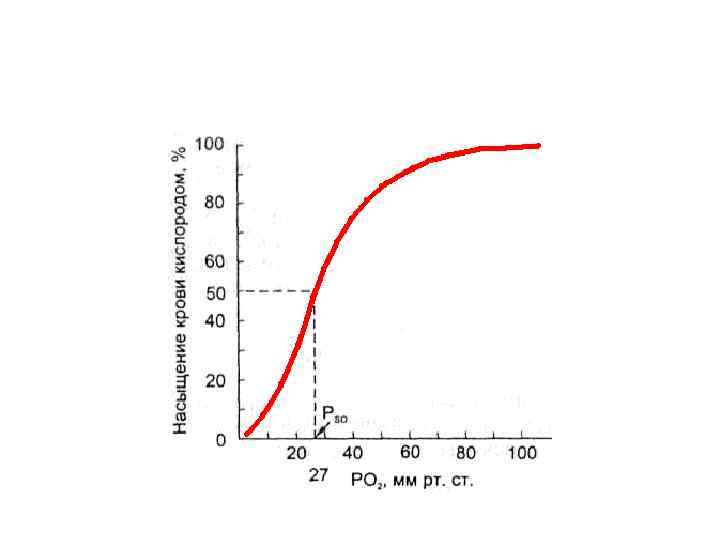

Вопрос 4 Кривая диссоциация оксигемоглобина

Вопрос 4 Кривая диссоциация оксигемоглобина